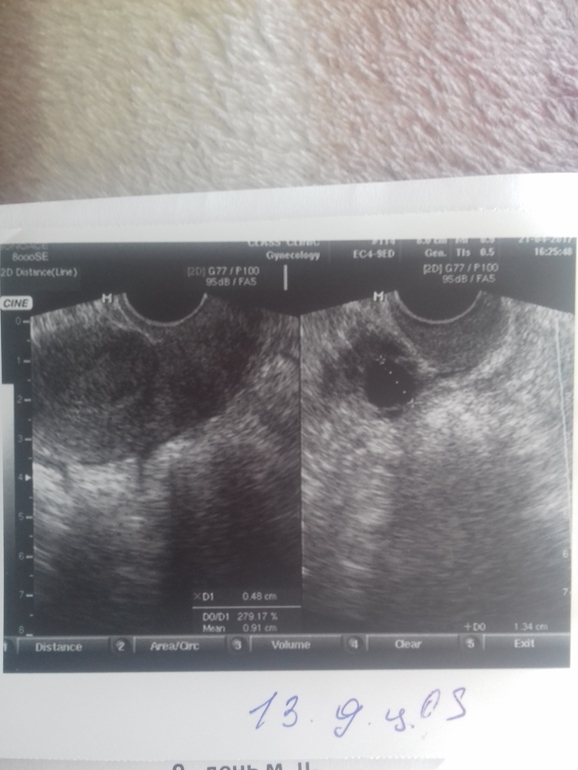

Всем доброго утра. Девочки мои дорогие,что можете сказать. Сегодня 15 д.ц. сходила на узи в другую клинику. Итог:фолликул 14×16.68 и эндометрий с 5 до 10 поднялся за 2 дня. Не знаю то ли ананасы помогли,то ли дивигель,но факт остается фактом. Фолликул растет медленно. Если на 13 д.ц. был 14×15мм. Это нормально вообще. А то за фоллик свой переживаю.